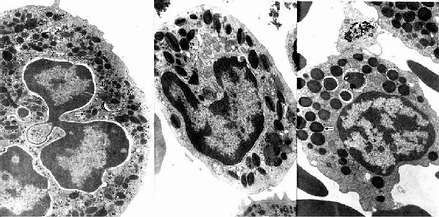

图5-5 人三种粒电镜像 ×17800

左图:中性粒细胞(白求恩医科大学尹昕、朱秀雄教授供图)

中图:嗜酸性粒细胞 左图:嗜碱性粒细胞

↑特殊颗粒,(

)嗜天青颗粒

中性粒细胞的胞质染成粉红色,含有许多细小的淡紫色及淡红色颗粒,颗粒可分为嗜天青颗粒和特殊颗粒两种。嗜天青颗粒较少,呈紫色,约占颗粒总数的20%,光镜下着色略深,体积较大;电镜下呈圆形或椭圆形,直径0.6~0.7μm,电子密度较高(图5-4,5-5),它是一种溶酶体,含有酸性磷酸酶和过氧化物酶等,能消化分解吞噬的异物。特殊颗粒数量多,淡红色,约占颗粒总数的80%,颗粒较小,直径0.3~0.4μm,呈哑铃形或椭圆形,内含碱性磷酸酶、吞噬素、溶菌酶等。吞噬素具有杀菌作用,溶菌酶能溶解细菌表面的糖蛋白。

2.嗜酸性粒细胞 嗜酸性粒细胞(eosinophilicgranulocyte,eosinophil)占白细胞总数的0.5%-3%。细胞呈球形,直径10~15μm,核常为2叶,胞质内充满粗大(直径0.5~1.0μm)、均匀、略带折光性的嗜酸性颗粒,染成桔红色(图5-2)。电镜下,颗粒多呈椭圆形,有膜包被,内含颗粒状基质和方形或长方形晶体(图5-4,5-5)。颗粒含有酸性磷酸酶、芳基硫酸酯酶、过氧化物酶和组胺酶等,因此它也是一种溶酶体。

3.嗜碱性粒细胞 嗜碱性粒细胞(basoophilic granulocyte,basophil)数量最少,占白细胞总数的0~15。细胞呈球形,直径10-12μm。胞核分叶或呈S形或不规则形,着色较浅。胞质内含有嗜碱性颗粒,大小不等,分布不均,染成蓝紫色,可覆盖在核上(图5-2)。颗粒具有异染性,甲苯胺蓝染色呈紫红色。电镜下,嗜碱性颗粒内充满细小微粒,呈均匀状或螺纹状分布(图5-4,5-5)。颗粒内含有肝素和组胺,可被快速释放;而白三烯则存在于细胞基质内,它的释放较前者缓慢。肝素具有抗凝血作用,,组胺和白三烯参与过敏反应。嗜碱性粒细胞在组织中可存活12-15天。